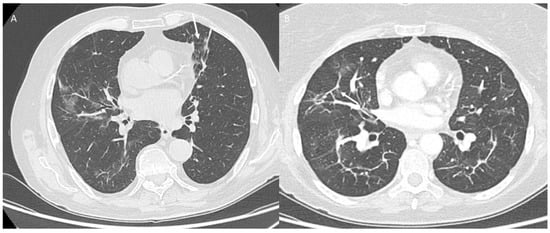

Pulmonary Lymphangitis Carcinomatosa

| Type of Pneumonia | Lung Involvement | CT-Patter |

|---|---|---|

| COVID-19 Pneumonia | Diffuse (related to the phase of disease) | ground-glass opacity, crazy-paving pattern, consolidative opacities, interlobular septal thickening (according to the phase of disease) |

| RRR-Related Vaccine | Target Area | Consolidative opacities |

| Pulmonary lymphangitis carcinomatosa | Diffuse (related to the phase of disease) | Irregularly interlobular septal thickening, smooth (early stage), or nodular thickening (late development), ground-glass opacity, pleural effusions. |

| ICI-Related Pneumonitis | Diffuse (related to the phase of disease) | ground-glass and reticular opacities, consolidative opacities, interlobular septal thickening, “crazy-paving” pattern |